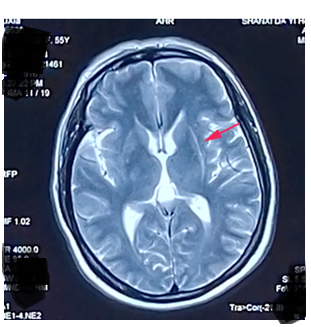

神经影像:壳核裂隙征你真的会吗?_多系统萎缩